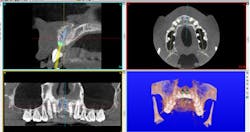

Author Gary Morris, DDS, tracked the paradigm shift from cement- to screw-retained implant restorations in his clinical prosthodontic practice. This was directly related to the introduction of angled implants (Co-Axis Implants, Southern Implants; figure 1). Co-Axis Implants were designed with angle offsetsGrowth of simultaneous extraction and molar implant placement

Anatomical constraints at implant sites often present a conflict between surgical and prosthodontic prerequisites for screw-retained implant-supported prostheses. Howes published the use of a dual-axis implant designed to help clinicians overcome these challenges by facilitating accurate surgical placement and prosthetic simplicity, as well as improved biomechanics and enhancedSince the authors have adopted accelerated treatment protocols with site-specific implants, they both have noted increased acceptance rates, as well as growth in implants placed and restored. Table 6 illustrates the increased acceptance rate for implant treatment in both practices. Data reflects patient acceptance of implant treatment at the first consultation/clinic visit.